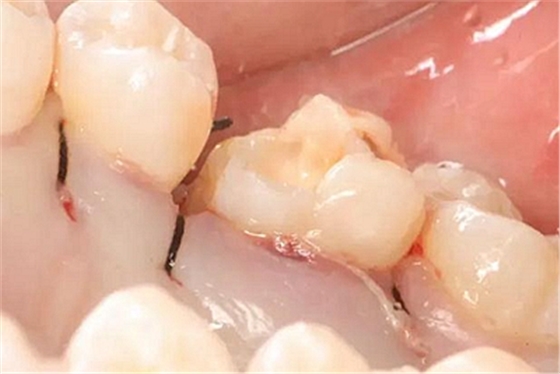

患者男性,35歲,B6銀汞充填后食物嵌塞,要求重新充填,口內(nèi)檢查見B6近中鄰頜面銀汞充填物,局部缺損,有繼發(fā)齲,去除原充填物及繼發(fā)齲,發(fā)現(xiàn)齲壞位于牙齦下方,給予冠延長手術(shù),同期嵌體預(yù)備,后一次性取模。(同樣設(shè)計為齦上邊緣)

硅橡膠取模后,灌注模型,科爾琥珀樹脂制作嵌體。

一周后拆線,口內(nèi)試戴合適,粘結(jié)嵌體。